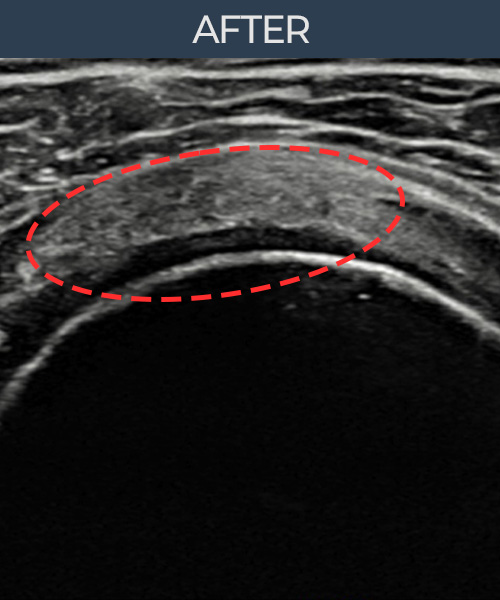

허ㅇㅇ님 · 우측 극상근건 관절면측 부분파열

우측 어깨 통증과 팔 들어올리기 제한으로 내원하셨습니다. 정밀 초음파 검사에서 극상근건 관절면측 부분파열이 확인되었고, 어깨인대 축소봉합술 시행 후 힘줄 연속성과 에코 패턴이 정상으로 회복되었습니다.